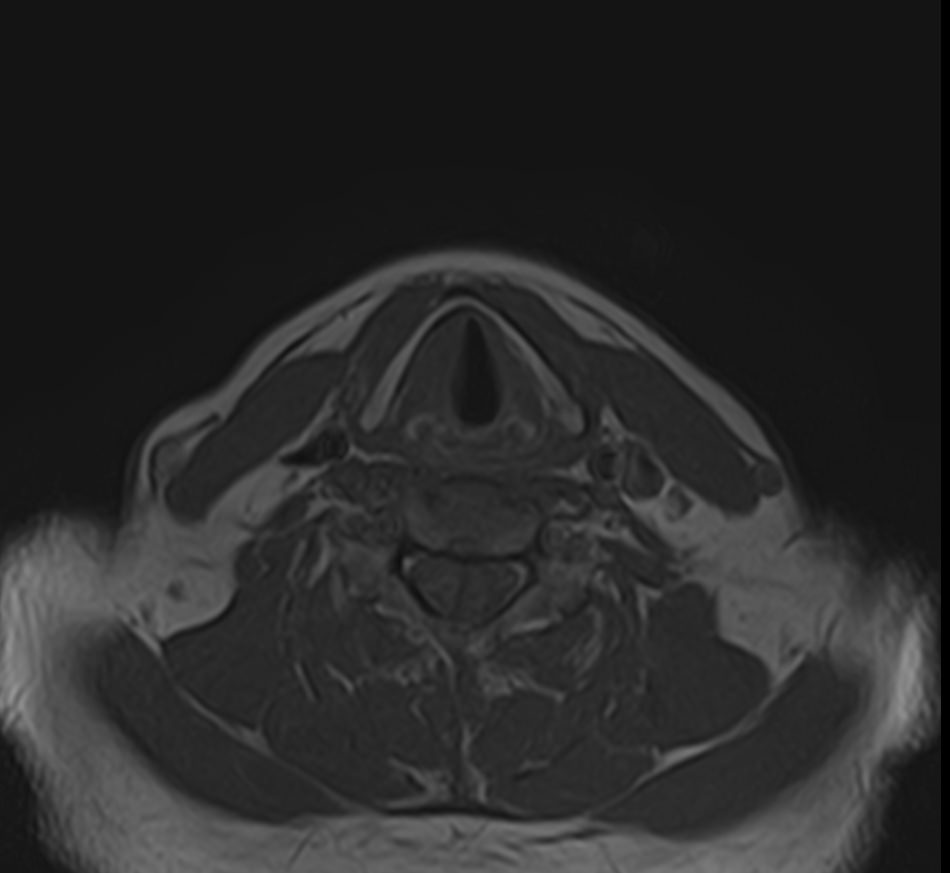

Магнитно-резонансная томография шеи предусматривает детальную визуализацию различных анатомических структур области шеи. Сюда входит полость рта, язык и корень языка, пищевод, гортань, окологлоточные лимфоузлы, шейные лимфоузлы, слюнные железы, щитовидная железа, мышцы и межфасциальные пространства.

В нашей клинике данное обследование выполняется на новейшем 32-канальном высокопольном томографе закрытого типа TOSHIBA VANTAGE TITAN 1,5 Тесла. Высокотехнологичный аппарат производит сканирование путем тончайших срезов с шагом от 1 мм в трех различных плоскостях. Используя современные компьютерные программы, полученные данные преобразуются в 3D-изображение исследуемой зоны. Это обеспечивает точность и достоверность диагностики заболеваний анатомических структур, расположенных в области шеи.